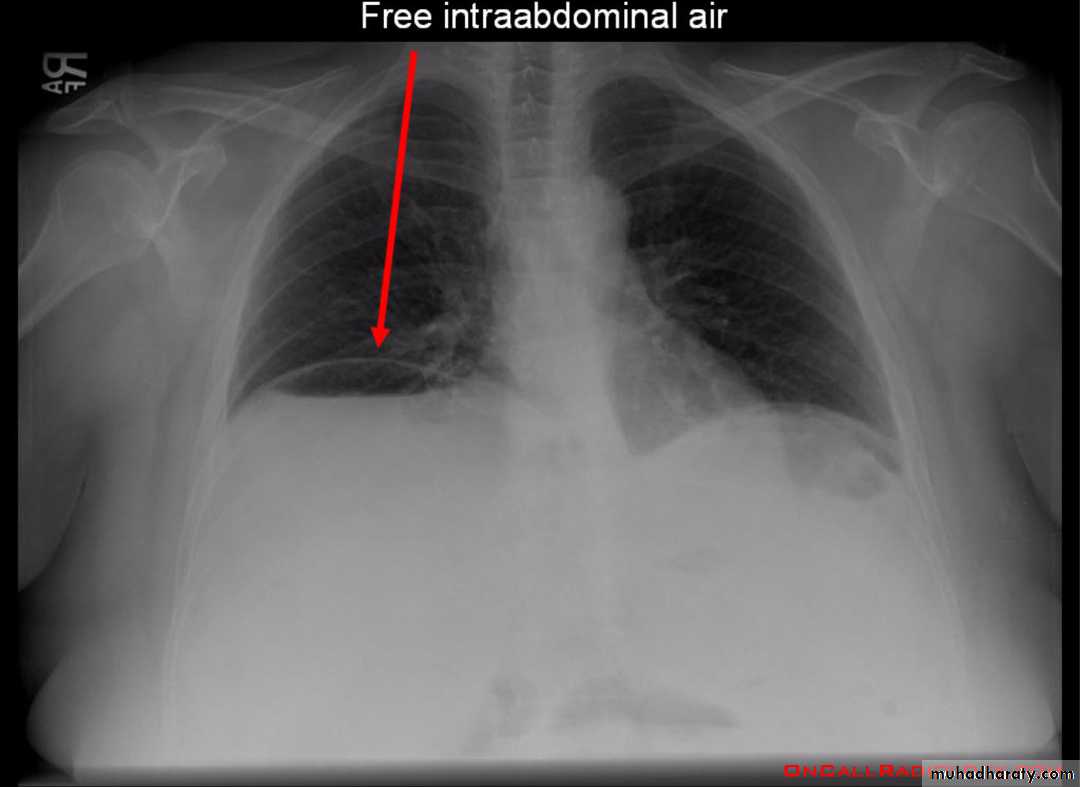

Pneumoperitoneum

describes as gas within the peritoneal cavity, and is often of a critical illnessplain film

Chest radiograph

An erect chest x-ray is probably the most sensitive plain radiograph for the detection of free intra peritoneal gas as crescent shape of lucency below diaphragm , more in the RT sided aspect .

Described as sub diaphragmatic free gas